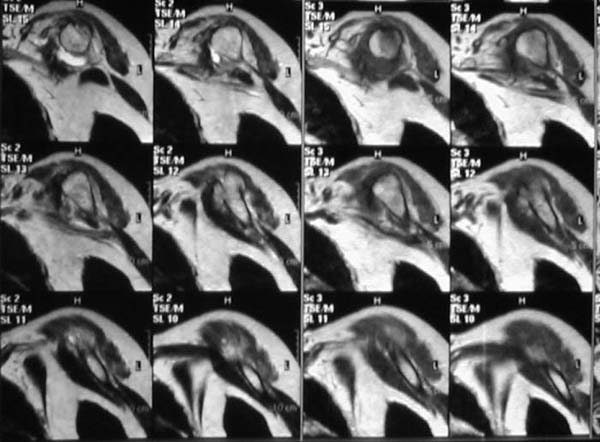

Активное отведение 80 гр., при пальпации - головка плечевой кости безболезненно вправляется и тут же самостоятельно вывихивается. Наложена косыночная иммобилизация, рентгенография (r3) и МРТ.В нашем диагностическом центре МРТ исследование плечевого сустава выполнено впервые, опыта у нас маловато :(.Вопросы: уточнение диагноза? какие исследования провести? тактика лечения?

Из того, что видно на недостаточно качественно отсканированных МРТ - нижний подвывих плеча и синовиит. Непонятный очаг по заднему контуру головки плеча (то ли артефакт, то ли косой срез, проходящий между головкой и большим бугорком). Сухожилия вращательной манжетки выглядят целыми. Неправильная форма нижней части labrum glenoidale - разрыв ?

И еще одно пожелание - МРТ костно-суставной системы ОБЯЗАТЕЛЬНО нужно проводить с использованием сканов с подавлением сигнала от жировой ткани (SPIR - на Филипсах, у Вас, как я вижу - Филипс; FATSAT - на других томографах, либо STIR - есть на любых аппаратах). Только так можно увидеть отек мягких тканей и костного мозга на фоне жировой ткани.

Плоскости при сканировании плеча обязательно должно быть 3

1. Ортогональная поперечная (аксиальная)

2. Косая корональная (параллельно длинной оси диафиза)

2. Косая сагиттальная (так же параллельно диафизу плеча)

МРТ должен показать разрыв манжетки, но признаться я не большой эксперт по чтению МРТ сканов, хотя затемнение, отек мягких тканей по задней поверхности плеча видны Обычные рентгенограммы демонстрируют остеолизис в области большого бугорка.

1. На рентгене - нижний подвывих плеча и очаг остеолиза суставного бугорка с четкими контурами (вдавленный перелом на фоне остеопороза ? доброкачественная опухоль? аваскулярный некроз ? (хотя ни разу не слышал об аваскулярном некрозе плеча..)

2.выраженный выпот в полости сустава

3. Сказать о связках и сухожилиях что-то при снимках в таком режиме не берусь.